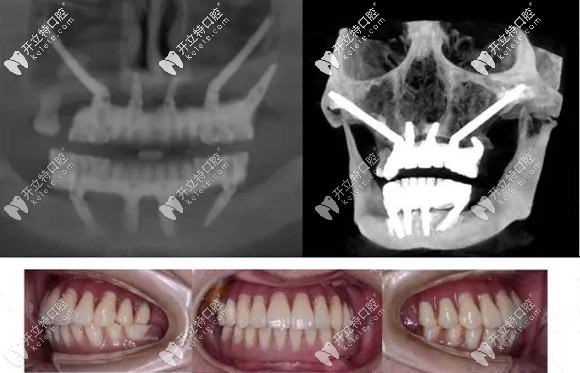

例如:術(shù)前采用專用軟件,結(jié)合患者口腔數(shù)據(jù),對(duì)種植方案進(jìn)行詳細(xì)手術(shù)設(shè)計(jì)。

采用3D打印患者上頜骨模型,在模型上先進(jìn)行摸擬手術(shù)。

制作手術(shù)導(dǎo)板,以便于在手術(shù)中進(jìn)行定點(diǎn)指導(dǎo)等措施。

做好術(shù)前準(zhǔn)備可避免穿顴穿翼種植并發(fā)癥的發(fā)生

正常情況,患者若身體條件許可,該種植技術(shù)是無(wú)需住院,無(wú)需全麻,也無(wú)需靜脈給藥鎮(zhèn)靜,在常規(guī)局部麻醉下就能進(jìn)行。

而且是局部小翻瓣,避免大翻瓣的創(chuàng)傷及術(shù)后較重的腫脹疼痛反應(yīng)。穿翼種植更是不翻瓣種植,術(shù)后即刻修復(fù),快速恢復(fù)咬合功能。

還可以消除對(duì)骨移植的需求,省去上頜竇提升手術(shù),縮短療程。